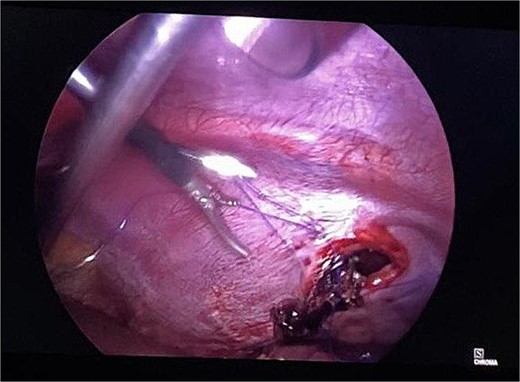

Routine examinations, including total blood counts, differential blood counts, renal function tests, and liver function tests, were within normal limits. The chest X-ray PA view showed the herniation of bowel loops into the left hemithorax with the collapse of the lower zone of the lung with no evidence of previous fracture (Fig. 1). Computed tomography (CT) showed a defect of size around 4 cm with evidence of protrusion of intra-abdominal content in the left hemidiaphragm with basal atelectasis of the left lung and mild dilatation of the jejunal bowel loops with a few air-fluid levels without a transition point (Fig. 2). The patient underwent laparoscopic left diaphragmatic hernia repair with mesh hernioplasty after 6 h of admission. The intraoperative findings revealed a defect of size 4 cm × 2 cm at the posterolateral aspect of the left hemidiaphragm with protrusion of the transverse colon, omentum, and part of the spleen with adhesions (Fig. 3). The content of the hernia was reduced, and primary repair of the defect was done (Fig. 4), and the defect was closed with a 10 × 15 cm intraperitoneal onlay composite mesh (Fig. 5). A postoperative X-ray showed no evidence of herniation of the bowel loops above the left hemidiaphragm (Fig. 6). He was discharged on the fourth postoperative day with oral medications. Follow-up in the outpatient department on the 14th postoperative day showed that he was doing well.

Intraoperative picture following reduction of hernia. The defect is being closed with prolene.